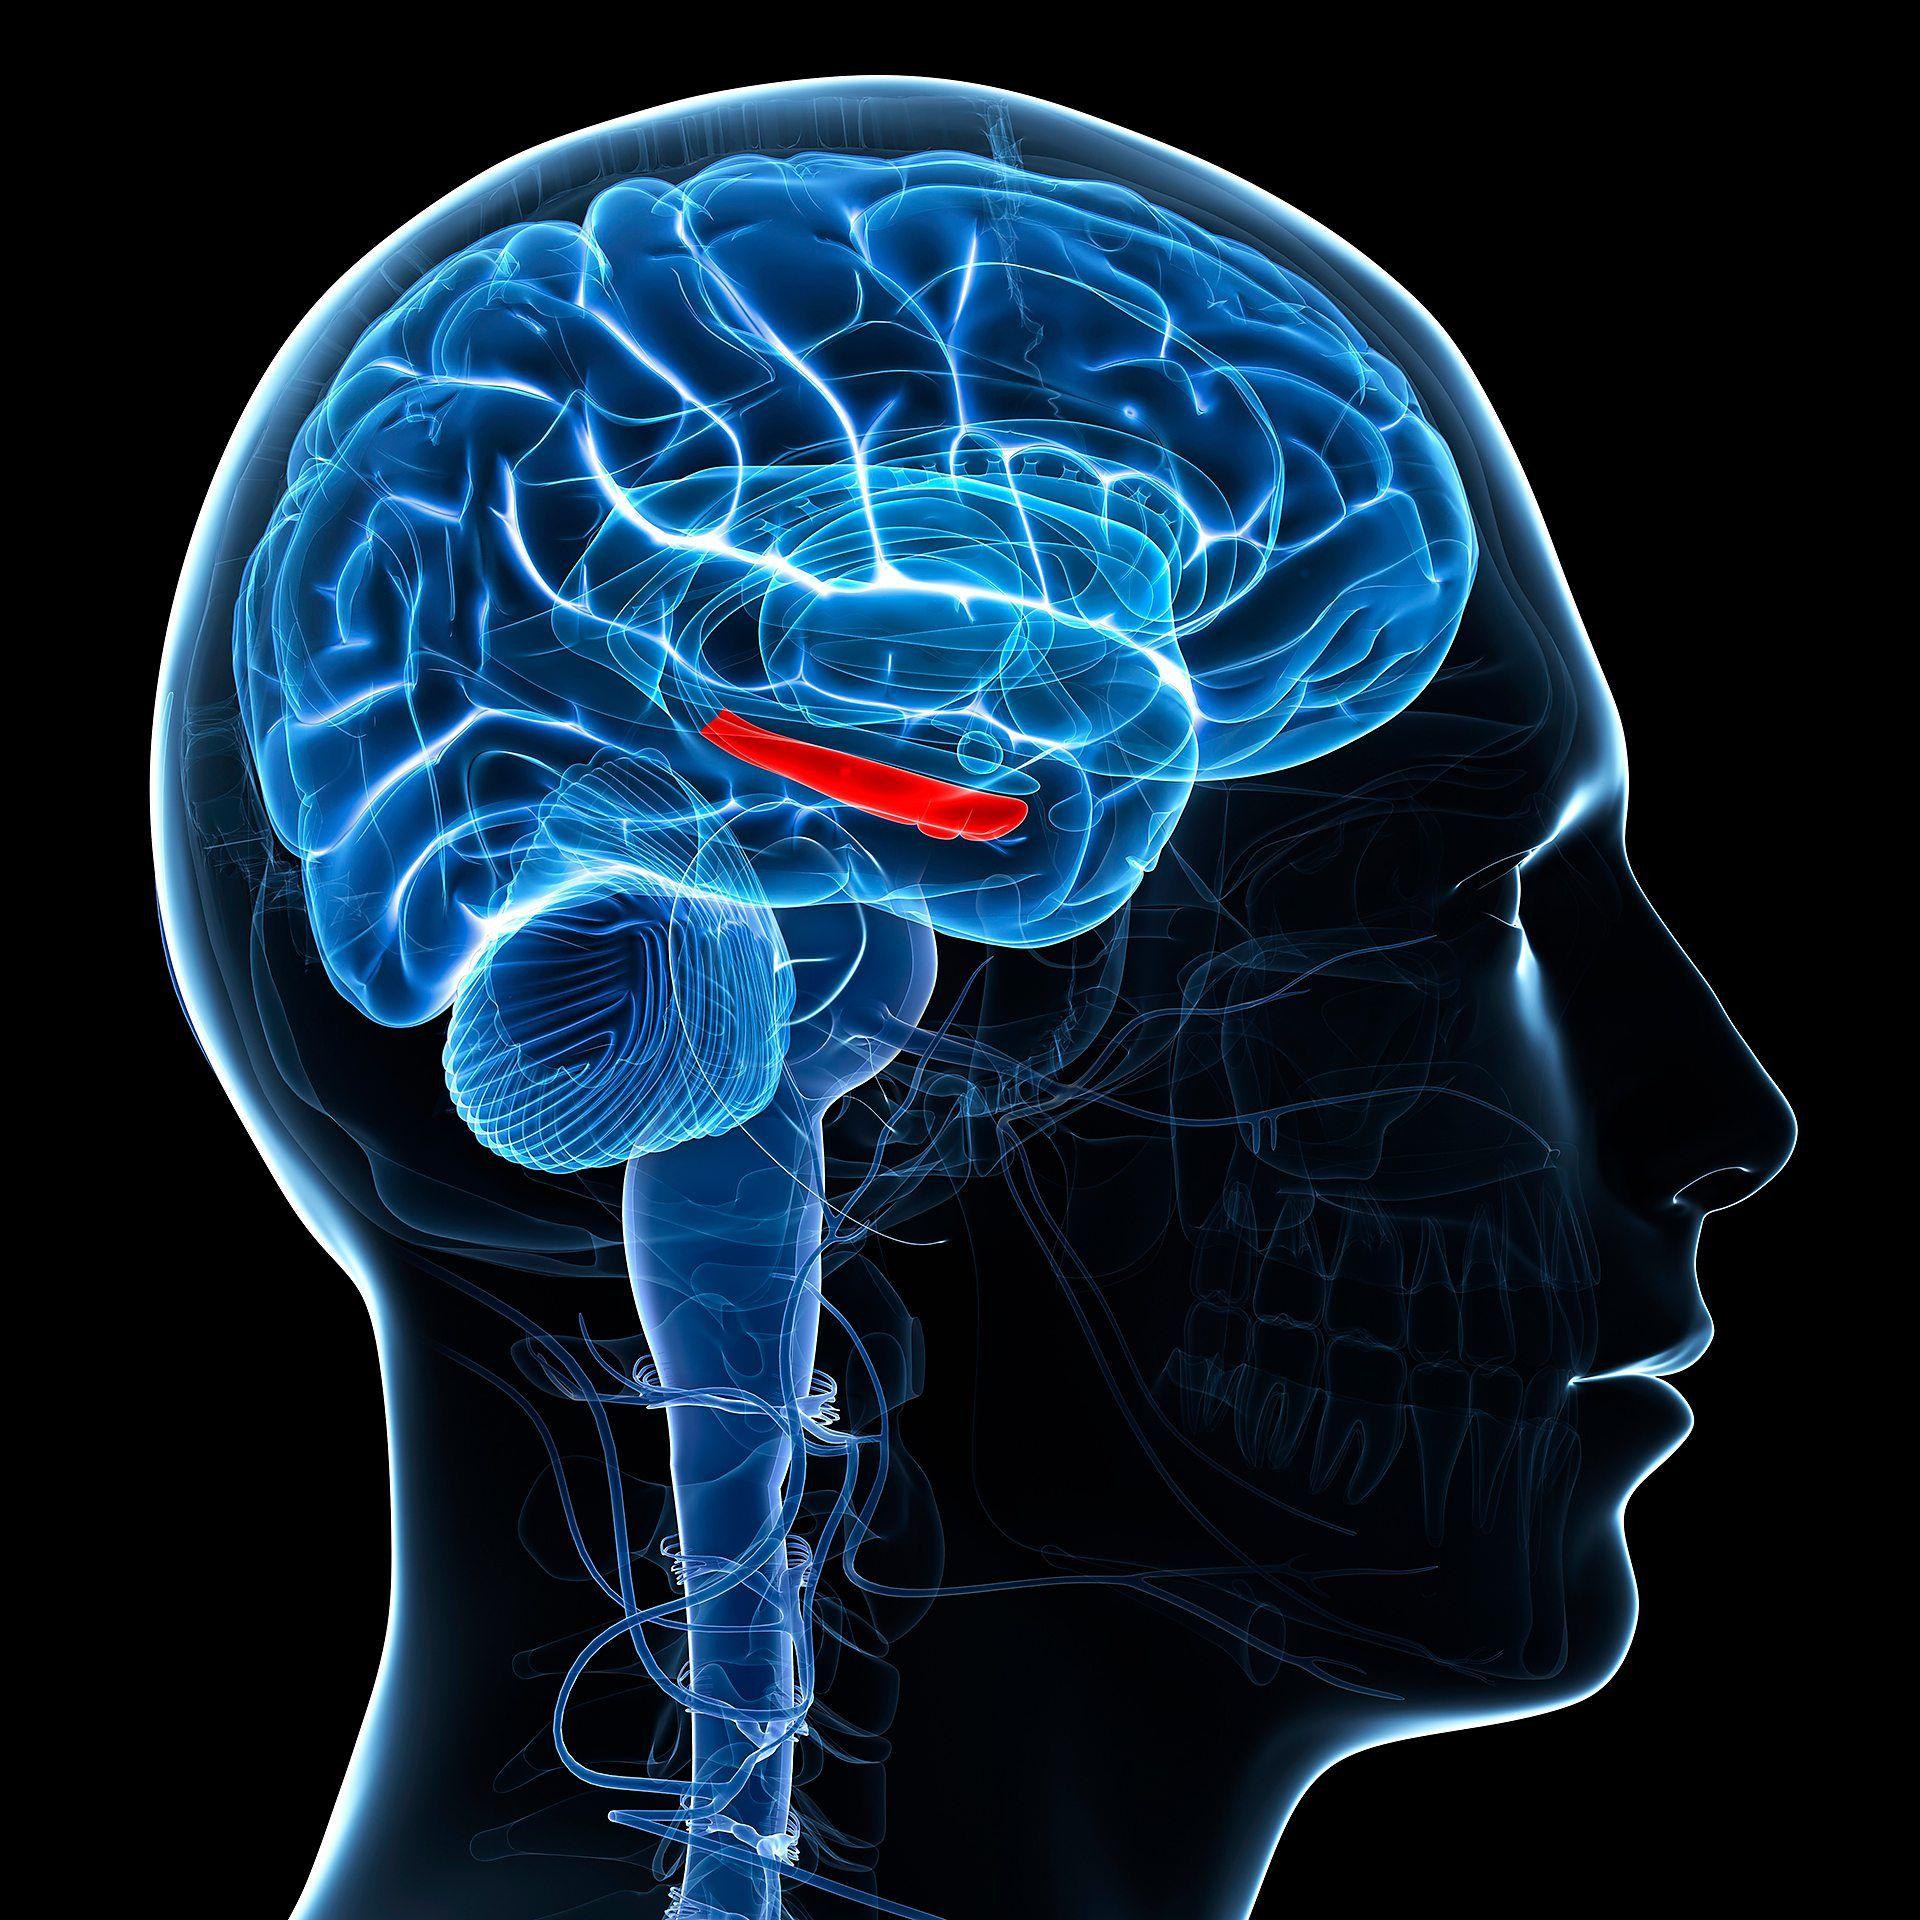

此外,運動還能強化大腦中負責記憶的重要區域——海馬體(hippocampus)。適度運動每週進行幾次,已被證實能增加海馬體的體積。其他研究也指出,運動的時機也很關鍵:在學習後四小時去散步,比立即運動更能改善記憶保留和後續提取能力。相比之下,拉伸運動則無法帶來記憶提升。

神經科學家觀察了14名受試者在運動後的大腦活動,發現腦細胞(神經元)之間出現微小的電活動爆發,即所謂的「腦漣漪」(brain ripples)。這些腦漣漪對鞏固記憶至關重要。

領導這項研究的愛荷華大學(University of Iowa)神經科學家蜜雪兒·沃斯(Michelle Voss)解釋,腦漣漪是許多神經元同時活化的現象,在睡眠和安靜休息時,對大腦如何打包和儲存記憶扮演關鍵角色。

研究團隊發現,運動後海馬體及其連接的其他腦區的腦漣漪明顯增加,且這些脈衝與大腦其他區域的神經活動同步性更高。研究人員認為,這有助於大腦鞏固記憶。